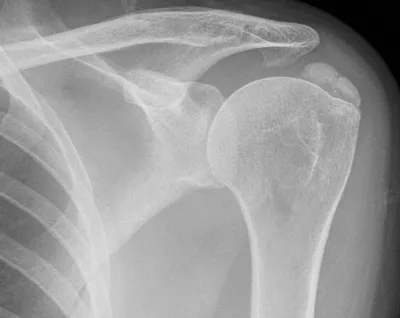

6 imagesCalcific tendinopathy of supraspinatus

XRAYShoulder

2/13/2026